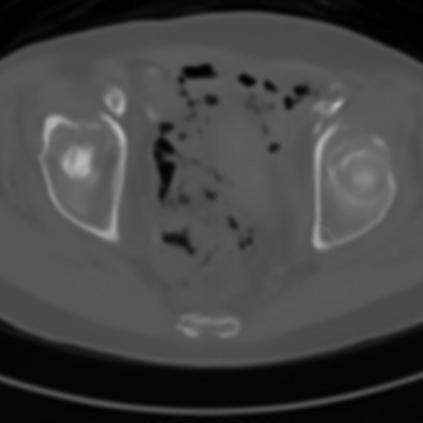

Sparse-view computed tomography (CT) -- using a small number of projections for tomographic reconstruction -- enables much lower radiation dose to patients and accelerated data acquisition. The reconstructed images, however, suffer from strong artifacts, greatly limiting their diagnostic value. Current trends for sparse-view CT turn to the raw data for better information recovery. The resultant dual-domain methods, nonetheless, suffer from secondary artifacts, especially in ultra-sparse view scenarios, and their generalization to other scanners/protocols is greatly limited. A crucial question arises: have the image post-processing methods reached the limit? Our answer is not yet. In this paper, we stick to image post-processing methods due to great flexibility and propose global representation (GloRe) distillation framework for sparse-view CT, termed GloReDi. First, we propose to learn GloRe with Fourier convolution, so each element in GloRe has an image-wide receptive field. Second, unlike methods that only use the full-view images for supervision, we propose to distill GloRe from intermediate-view reconstructed images that are readily available but not explored in previous literature. The success of GloRe distillation is attributed to two key components: representation directional distillation to align the GloRe directions, and band-pass-specific contrastive distillation to gain clinically important details. Extensive experiments demonstrate the superiority of the proposed GloReDi over the state-of-the-art methods, including dual-domain ones. The source code is available at https://github.com/longzilicart/GloReDi.